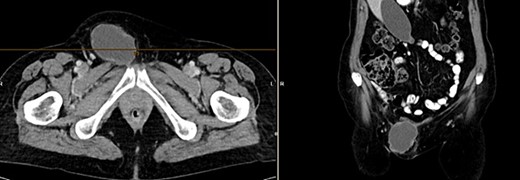

The CT of the abdomen showed a highly suspicious malignant mass in the left groin area (Fig 3). Additionally, nearby satellite lesions were detected, interpreted as lymph nodes. During a more thorough physical examination, a hazelnut-sized, highly suspicious malignant lesion was identified on the glans penis. Upon detailed anamnesis, the patient reported a previous circumcision surgery with carcinoma detection.

Finding from CT of the abdomen: highly suspicious malignant mass in the left groin area, with nearby satellite lesions, DD lymph nodes.